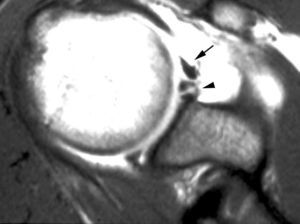

ALPSA (anterior labroliamentous periosteal avulsion)

Al igual que en el apartado anterior, existe también una separación de LG junto con la cápsula y el periostio, pero a diferencia de las lesiones de Bankart o Perthes, el LG se desplaza hacia dentro, por detrás del borde de la glenoides18 (fig. 12). La lesión de ALPSA puede cicatrizar por sinovialización (fig. 12), pero continúa siendo de carácter inestable.

Fig. 12.--ALPSA (anterior labroliamentous periosteal avulsion) agudo (A) y crónico (B). Nótese la separación del labio glenoideo y su desplazamiento posterior y medial por detrás del reborde glenoideo (flecha en A). En una fase crónica el labio glenoideo no se distingue como una estructura separada, sino como un engrosamiento de la unión entre el labio, la cápsula y el periostio (flecha en B).